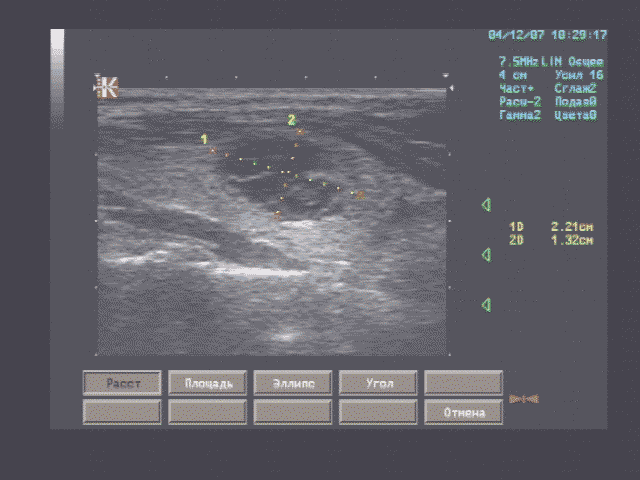

Печень - границы печени не расширены: нижний край правой доли у рёберной дуги, незначительно закруглён, переднезадний размер правой доли 119 мм, косой вертикальный 148 мм, переднезадний размер левой доли 59 мм, вертикальный 93 мм; контуры ровные, диафрагмальный контур нечёткий, паренхима неоднородная за счет гипоэхогенного участка вблизи правой боковой стенки желчного пузыря, имеющего округлую форму, диаметром 15 мм, имеющего ровные, относительно четкие контуры, однородное внутреннее строение; на остальном протяжении паренхима однородная, эхоструктура диффузно повышенной эхогенности рисунок зернистости нечёткий; внутрипечёночные жёлчные протоки не расширены, свободны, сосудистый рисунок обеднен.

Эхографические признаки хронического гепатита, гипоэхогенного очага 5 сегмента печени.